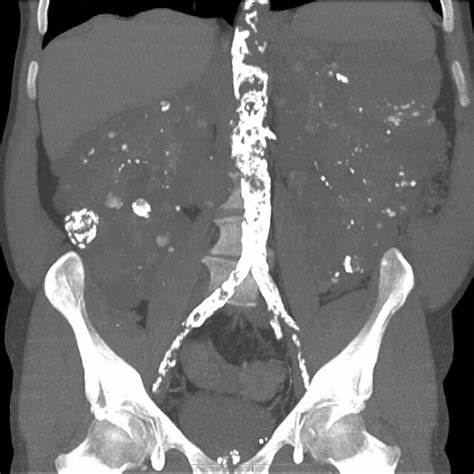

calcification: The process by which calcium salts build up in body tissue, causing the tissue to harden. This often occurs in bones but can also happen in soft tissues as part of disease processes.

calculus: A hard, stone-like deposit formed in a body organ, often referring to kidney stones, gallstones, or dental plaque.

calculi: Plural of “calculus,” referring to small, hard deposits of minerals that can form in various parts of the body, such as kidney stones or gallstones.

calculous: Relating to or characterized by the presence of calculi (stones), especially in the organs or ducts, such as in the gallbladder or kidneys.